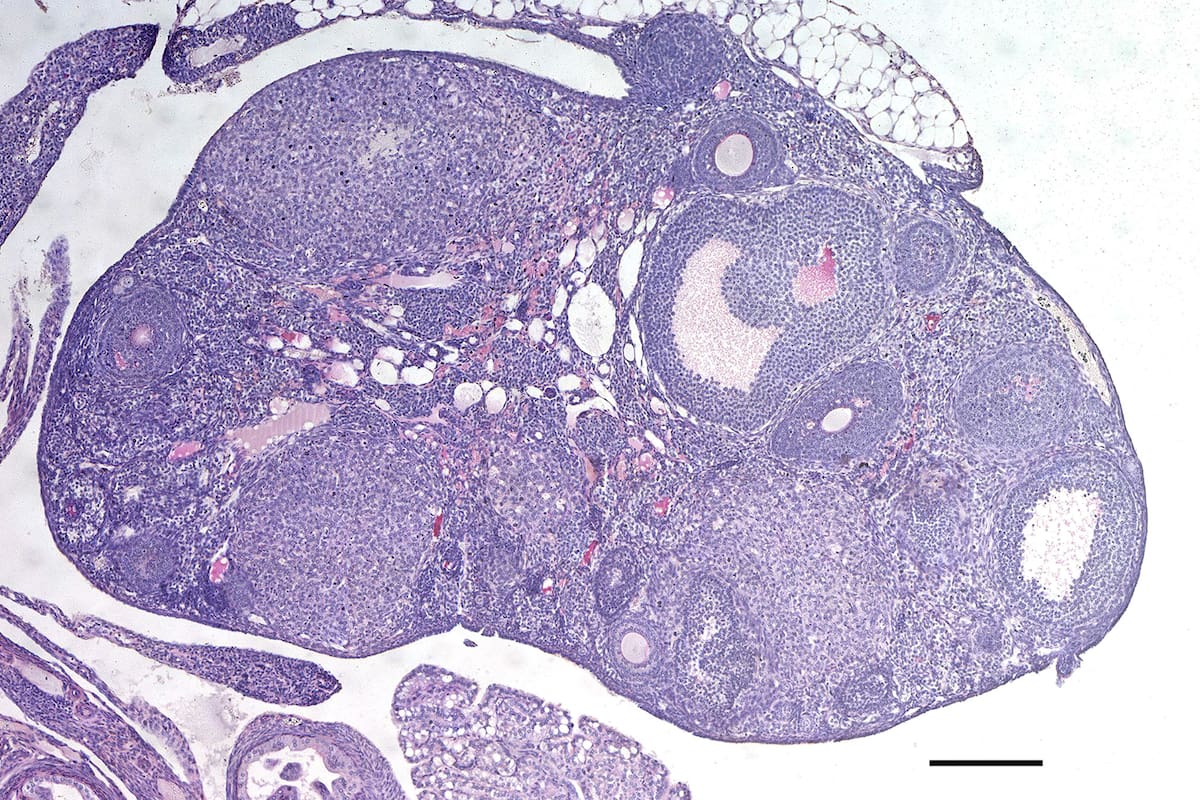

MADRID.— Las mujeres y las hembras de todos los mamíferos nacen con un número determinado de óvulos. El agotamiento de las reservas indica el fin de su edad reproductiva. Ahora, un amplísimo grupo de científicos ha identificado 290 zonas del genoma humano que influyen en la llegada de la menopausia. Ello permitió alargar la fertilidad en ratones modificando los mismos genes. En un futuro, esta información podría permitir saber cuándo se va a producir la senescencia reproductiva e incluso retrasarla.

En un enorme esfuerzo, 300 científicos de todo el mundo han estudiado el genoma de más de medio millón de mujeres conservado en varias bases de datos. Buscaban variaciones en el ADN que estuvieran relacionadas con la aparición temprana o tardía de la menopausia. El trabajo, publicado hoy en la revista Nature, encontró al menos 290 variantes en aquellas mujeres con un fin de la vida reproductiva que se alejaba de la edad media, ya fuera por exceso o por defecto. La cifra supone multiplicar por cinco las modificaciones genéticas que se sabía afectaban a la fertilidad natural.

Además del incremento de variaciones genéticas conocidas que afectan a la menopausia, este trabajo ha destacado la conexión entre esta senescencia ovárica y los mecanismos que regulan la reparación del ADN de las células o la propia muerte celular, la llamada apoptosis, cuando las células se suicidan si algo va mal. Lo explica Roig: “La gran mayoría de los genes que identificamos de estos 290 están involucrados en la reparación del ADN dañado”. En otros tejidos y partes del cuerpo humano, lo que hacen es corregir errores o fallos a nivel genético provocados por factores internos o ambientales. “Nosotros encontramos genes de reparación del ADN relacionados con la aparición de la menopausia que funcionan de varias maneras diferentes: desde la etapa de replicación del ADN cuando se genera la reserva de óvulos en el feto, hasta la reparación de roturas en el ADN que se hacen para introducir variabilidad genética en los óvulos durante un proceso llamado meiosis, también en etapas fetales”, detalla Roig.

Pero además hay una concentración de variaciones en una cincuentena de genes que intervienen en la muerte celular. “Cuando una célula sufre daño en su ADN, la maquinaria de reparación del ADN activa mecanismos de bloqueo de la progresión del ciclo celular para dar tiempo a la célula a reparar el daño. Si esto no puede darse, se activan mecanismos de apoptosis con tal de eliminar esta célula dañada y evitar problemas para el organismo. Del mismo modo, estos procesos también ocurren en los óvulos”, comenta Roig.

Toda esta nueva información permitió a los científicos cambiar la duración de la vida reproductiva de ratones modificados para portar alguna de estas mutaciones y así bloquear o activar determinados genes. Es el caso de dos genes, CHEK1 y CHEK2, que regulan diversos procesos de reparación del ADN. Al eliminar uno de ellos, el CHEK2, para que dejara de funcionar o potenciar al otro gen, CHEK1, para aumentar su actividad, observaron un incremento del 25% de la duración de la vida reproductiva en los ratones, con un mayor número de óvulos en los roedores mutantes.